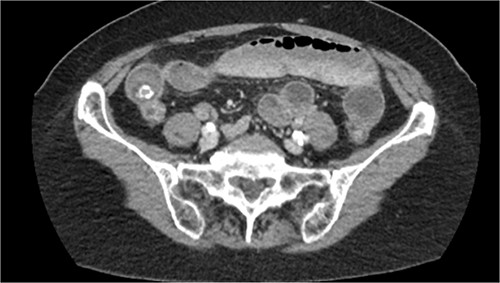

On physical exam, the abdomen was notable for diffuse periumbilical tenderness without guarding, rigidity or any palpable masses. Laboratory studies were all within normal limits. CT scan of the abdomen and pelvis with IV contrast demonstrated a small bowel obstruction, secondary to gallstone ileus with a severely inflamed gallbladder and fistulization to the duodenum and hepatic flexure of the colon (see Fig. 1). Two gallstones were identified within the ileum, 2 and 2.5 cm in size. Surgery was consulted, and a small bowel enterotomy was planned to retrieve the obstructing stone.